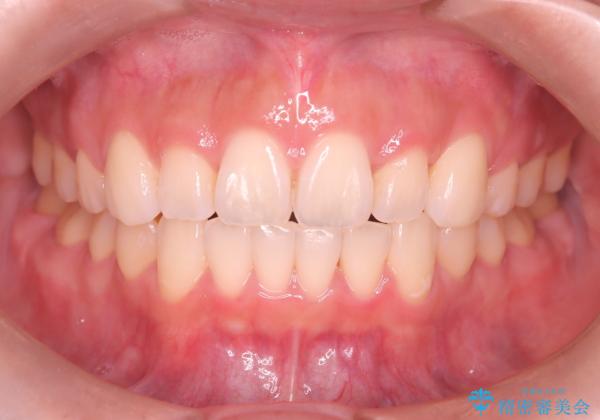

- 前歯の凸凹と口元の突出感を主訴に来院されました。

臼歯関係が上顎前突傾向のため、上の小臼歯を抜歯してワイヤー矯正を行なっております。

下顎の叢生はIPRを行なって配列しています。